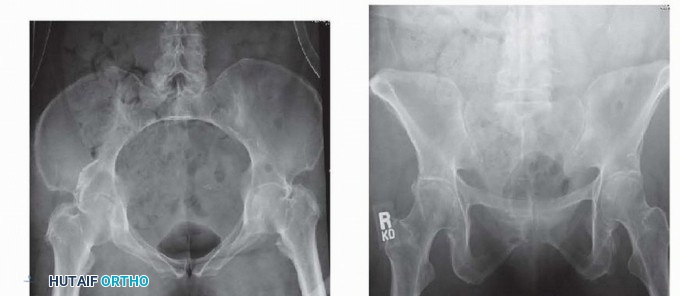

### FIG 2 • Examples of the anatomic variants between genders. The female pelvis has a more concave shape to the ring and the pubic arch has less of an acute angle because of the broader pubic body, as demonstrated in the inlet (A) and outlet (B) views of a female pelvis. The male pelvic ring is more oval, with a much more acute angle anteriorly because of the thinner pubic body, as seen the corresponding inlet (C) and outlet (D) views. Occasionally, lateral compression injuries involve fractures of the pubic rami and a symphyseal disruption. This occurs when the compressed hemipelvis causes the contralateral rami to fracture and the contralateral symphyseal body to tilt inferiorly. Because one side of the symphysis is off and can compress the bladder or uterus, altering the pelvic ring, it should be reduced to the other pubic body, which remains intact.

### FIG 5 • Appropriate AP (A), inlet (B), outlet (C), and Judet views (D,E) of the pelvis in a patient with pelvic trauma and wide pubic symphysis. (Courtesy of Jodi Siegel, MD, and David Templeman, MD.) 329 ## DIFFERENTIAL DIAGNOSIS Rami fractures Symphyseal strain Hip fracture Muscle strain or avulsion Lumbar fracture ## ACUTE MANAGEMENT The patients should be hemodynamically stabilized. The pelvis can be stabilized by placing ankles together with Ace wraps. Heels and ankles should be padded to prevent skin breakdown and ulcer formation. Placing a sheet across the pelvis at the level of the greater trochanters can be used to reduce the symphysis and temporarily stabilize the pelvis. The sheet can be affixed with towel clips to hold it with tension rather than tying a knot across the abdomen (see Cha 33). A pelvic binder can also be used in the same manner, but the authors prefer the sheet technique. ## NONOPERATIVE MANAGEMENT If minimal separation of the symphysis is present, the patient can be made non-weight bearing on the affected side and can be allowed to ambulate. Close radiographic monitoring should ensue, with weekly radiographs. Single-leg stance views can be used to help identify late instability. ## SURGICAL MANAGEMENT A diastasis larger than 2.5 mm indicates a disruption of the sacrospinous ligaments and thus an unstable pelvis. Open fixation of the symphysis stabilizes the anterior pelvis. 3 Open injuries can be stabilized with external fixation using iliac wing pins or Hanover pins placed at the level of the anterior inferior iliac spine. Refer to Chapter 33 for more details. Additionally, the technique of INFIX using pedicle screws at the anterior inferior iliac spine and a subcutaneously placed bar can also be used for obese patients. 17 In APC type II injuries with an intact hemipelvis, no posterior fixation is needed, and the symphysis is reduced and stabilized first. For type III injuries, if the innominate bone is broken, the anterior pelvic ring is reduced and fixed after the posterior ring is reduced and fixed. The anterior pelvic ring is reduced and fixed as a first step if the innominate bone remains intact. Indications for anterior stabilization for vertically unstable pelvic fractures include improving anterior stability to the pelvic ring, stabilizing a pelvic injury that is associated with an injury requiring a laparotomy, treatment of bone protruding into the perineum (ie, a tilt fracture), or in association with an acetabular fracture requiring open reduction. 13 ## Preoperative Planning The surgeon should review appropriate radiographic studies (AP, inlet, and outlet views and CT scan). Identifying all rami fractures and the presence of any pubic body fractures is essential, as this will help determine how to obtain a reduction as well as dictate the type of fixation necessary. The surgeon should plan to obtain stress views in the operating room to determine the stability of the pelvis if there is any question of stability. The surgeon should rule out the presence of a bladder rupture or urethral tear. If one is present, repair should be performed at the same time as internal fixation of the symphysis, if possible, to avoid a more complex late reconstruction. Any history of previous abdominal surgery or the presence of prior incisions should be identified before going to the operating room. The proper equipment must be available, such as C-arm, radiolucent table, large bone clamps, external fixation equipment, and a C-clam ## Positioning 330 The patient is placed on a radiolucent flat-top table with legs together to facilitate reduction of the symphysis. Fluoroscopic radiographs confirming the ability to obtain a good inlet and outlet views with the C-arm are obtained before preparing and draping the patient. Right-handed surgeons may prefer to have the C-arm on the patient's right side and the drill and instruments on the patient's left for easier access to the symphysis with the drill. Placement of a Foley catheter is needed to decompress the bladder; it can also be felt intraoperatively to help identify the bladder. Venodyne boots are placed on both legs if possible for deep vein thrombosis prophylaxis during the case. ## Approach Open reduction of the symphysis is performed with an anterior Pfannenstiel approach. ## TECHNIQUES